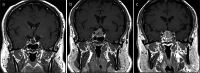

Primary non-neuroendocrine tumours of the pituitary gland and sella are rare lesions often challenging to diagnose. We describe two cases of clinically aggressive primary glomus tumour of the pituitary gland. The lesions occurred in a 63-year-old male and a 30-year-old female who presented with headache, blurred vision and hypopituitarism. Neuroimaging demonstrated large sellar and suprasellar tumours invading the surrounding structures. Histologically, the lesions were characterised by angiocentric sheets and nests of atypical cells that expressed vimentin, smooth muscle actin and CD34. Perivascular deposition of collagen IV was also a feature. Case 2 expressed synaptophysin. INI-1 (SMARCB1) expression was preserved. Both lesions were mitotically active and demonstrated a Ki-67 labelling index of 30%. Next-generation sequencing performed in case 1 showed no mutations in the reading frame of 37 commonly mutated oncogenes, including BRAF and KRAS. Four pituitary glomus tumours have previously been reported, none of which showed features of malignant glomus tumour. Similar to our two patients, three previous examples displayed aggressive behaviour.